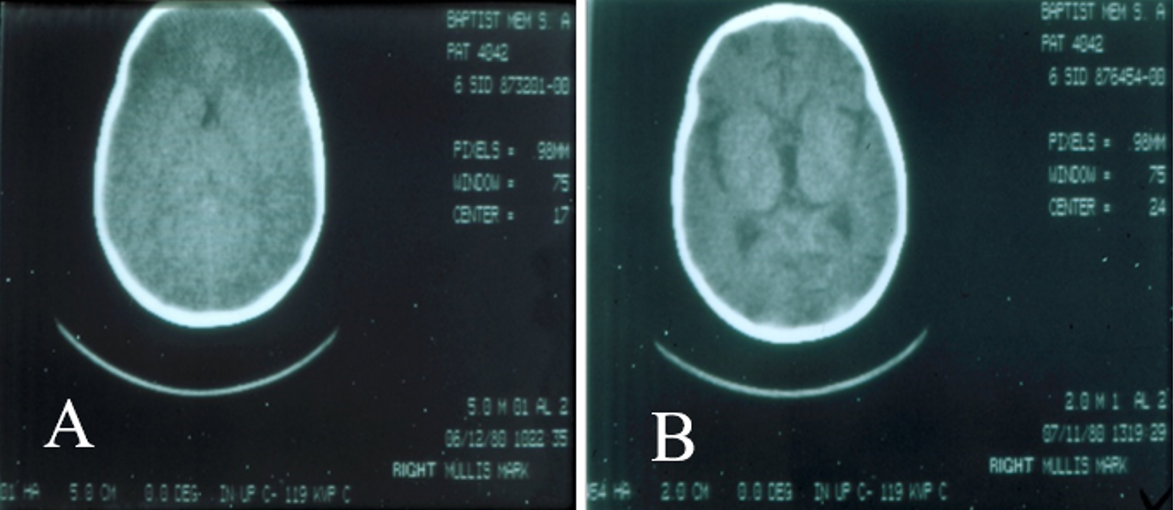

Children are prone to “fluid creep,” a term that describes the insidious trend of infusing volumes larger than predicted by conventional formulas, particularly the Parkland formula. Recent studies have reported crystalloid fluid resuscitation volumes ranging from 4.8 to 6.7 mL/kg/%TBSA for the initial 24 hours post-burn.12 Excessive resuscitation promotes fluid extravasation into burned and unburned tissue that can result in massive facial and airway swelling requiring intubation, decreased chest wall compliance, pulmonary edema and congestive heart failure, burn wound conversion, cerebral edema (Figure 3), anterior ischemic optic atrophy and blindness, and extremity and abdominal compartment syndromes.

Figure 3. (A) Computed tomography scan of a child obtunded from a house fire; the ventricular system is compressed. (B) Same child 1 month later, lucid and restored to an edema-free brain. (Courtesy of Dr BA Pruitt)